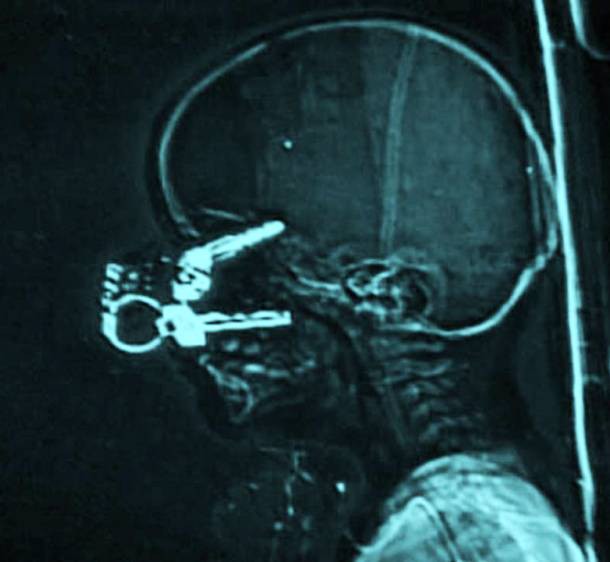

13. Chiếc chìa khóa cắm trên mặt

Tới tận bây giờ, người ta vẫn không thể hiểu được điều gì đã xảy ra với đứa trẻ 17 tháng tuổi tên Nicholas Holderman này. Người mẹ bất cẩn đã biến "Holderman" thành "Key-Holderman" khi vô tình làm chùm chìa khóa cắm sâu vào gương mặt cậu bé đáng thương này. Và may mắn thay, sau khi được cứu chữa kịp thời, cậu bé này vẫn vượt qua tất cả và lớn lên khỏe mạnh, bình thường.